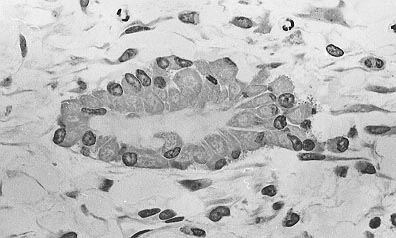

Cells called osteoblasts (gray blobs forming an oval) create new bone tissue.

Cells called osteoclasts break down old bone through a process called resorption. Other cells called osteoblasts take charge of making new bone. But most bone cells belong to a third type. Called osteocytes, they tell the osteoblasts and osteoclasts what to do. “If you think of remodeling as a symphony, the osteocyte is the conductor,” Johnson explains.

Cells called osteocytes, one shown here, act like conductors in a symphony, instructing the other bone cells what to do.